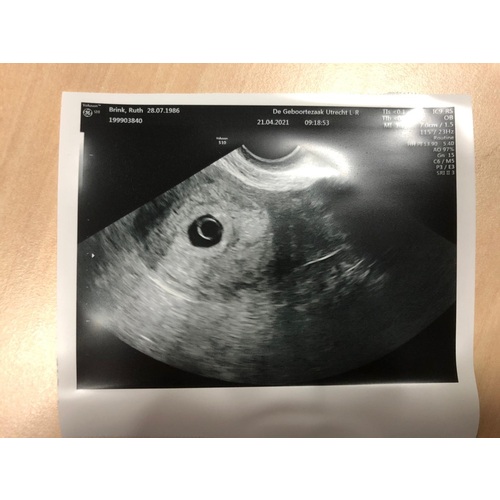

Geen stress proberen te hebben. Dit ziet er precies uit als 'n echo met ruim 5 weken. Jammer dat je je op iets anders had ingesteld en dan is 't begrijpelijk dat je daar stress van hebt. Maar wat je nu ziet is gewoon passend, waarschijnlijk verklaarbaar door 'n latere ovulatie/ innesteling en de volgende echo zal dit kleins vast gegroeid zijn! Dus probeer weer tot rust te komen en op naar de volgende echo! Veel geluk gewenst馃崁